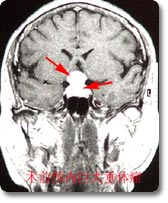

治愈率处于国内领先水平。引进德国Zeppelin公司先进的神经内镜手术治疗系统,建立了神经内窥镜微创手术中国培训基地,开展了神经内窥镜经单鼻孔切除垂体瘤、脑积水、蛛网膜囊肿、脑室内肿瘤、颅内血肿,听神经瘤等手术,特别是在经单鼻孔蝶窦入路切除垂体瘤方面经验极为丰富,治疗病人800余例,治愈率处于国内领先水平。神经内镜微创手术具有手术创伤小、无出血、手术危险小、术后康复快、住院时间短、费用低等多项优点。